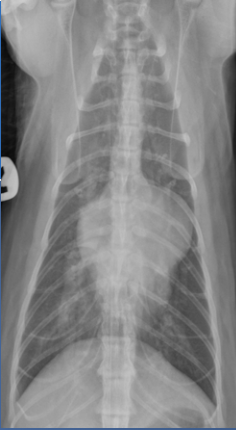

what is wrong

PAH, pulmonary arterial hypertension. see large RV, RA, pulmonary artery.